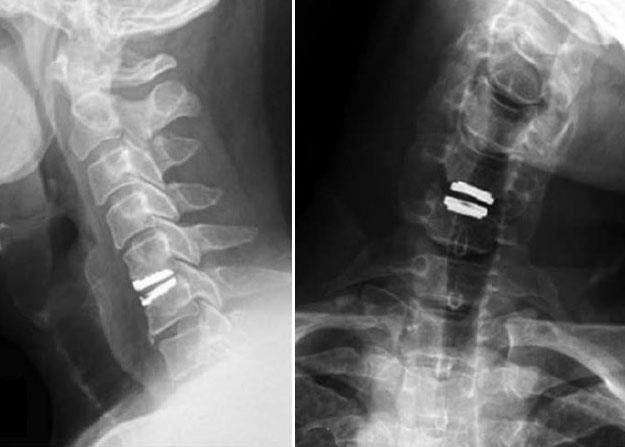

3. Artificial Disk Replacement (ADR)

This procedure involves removing the degenerated disc and replacing it with artificial parts, as is done in hip or knee replacement. The goal of disc replacement is to allow the spinal segment to keep some flexibility and maintain more normal motion, which may relieve some pressure on the adjacent disc levels and prevent them from premature failure.

Similar to ACDF, an "anterior" approach is used for the surgery. The problematic disc level is removed after confirmation with intra-operative X-ray, and then an artificial disc implant is inserted into the disc space. The implant is made of all metal, metal and plastic, or metal and ceramic. It is designed to maintain motion between the vertebrae after the degenerated disc has been removed. The implant may help restore the height between the vertebrae and widen the passage for the nerve roots to exit the spinal canal.

orthoinfo.aaos.org

Side and front view of patient with artificial disc replacement.